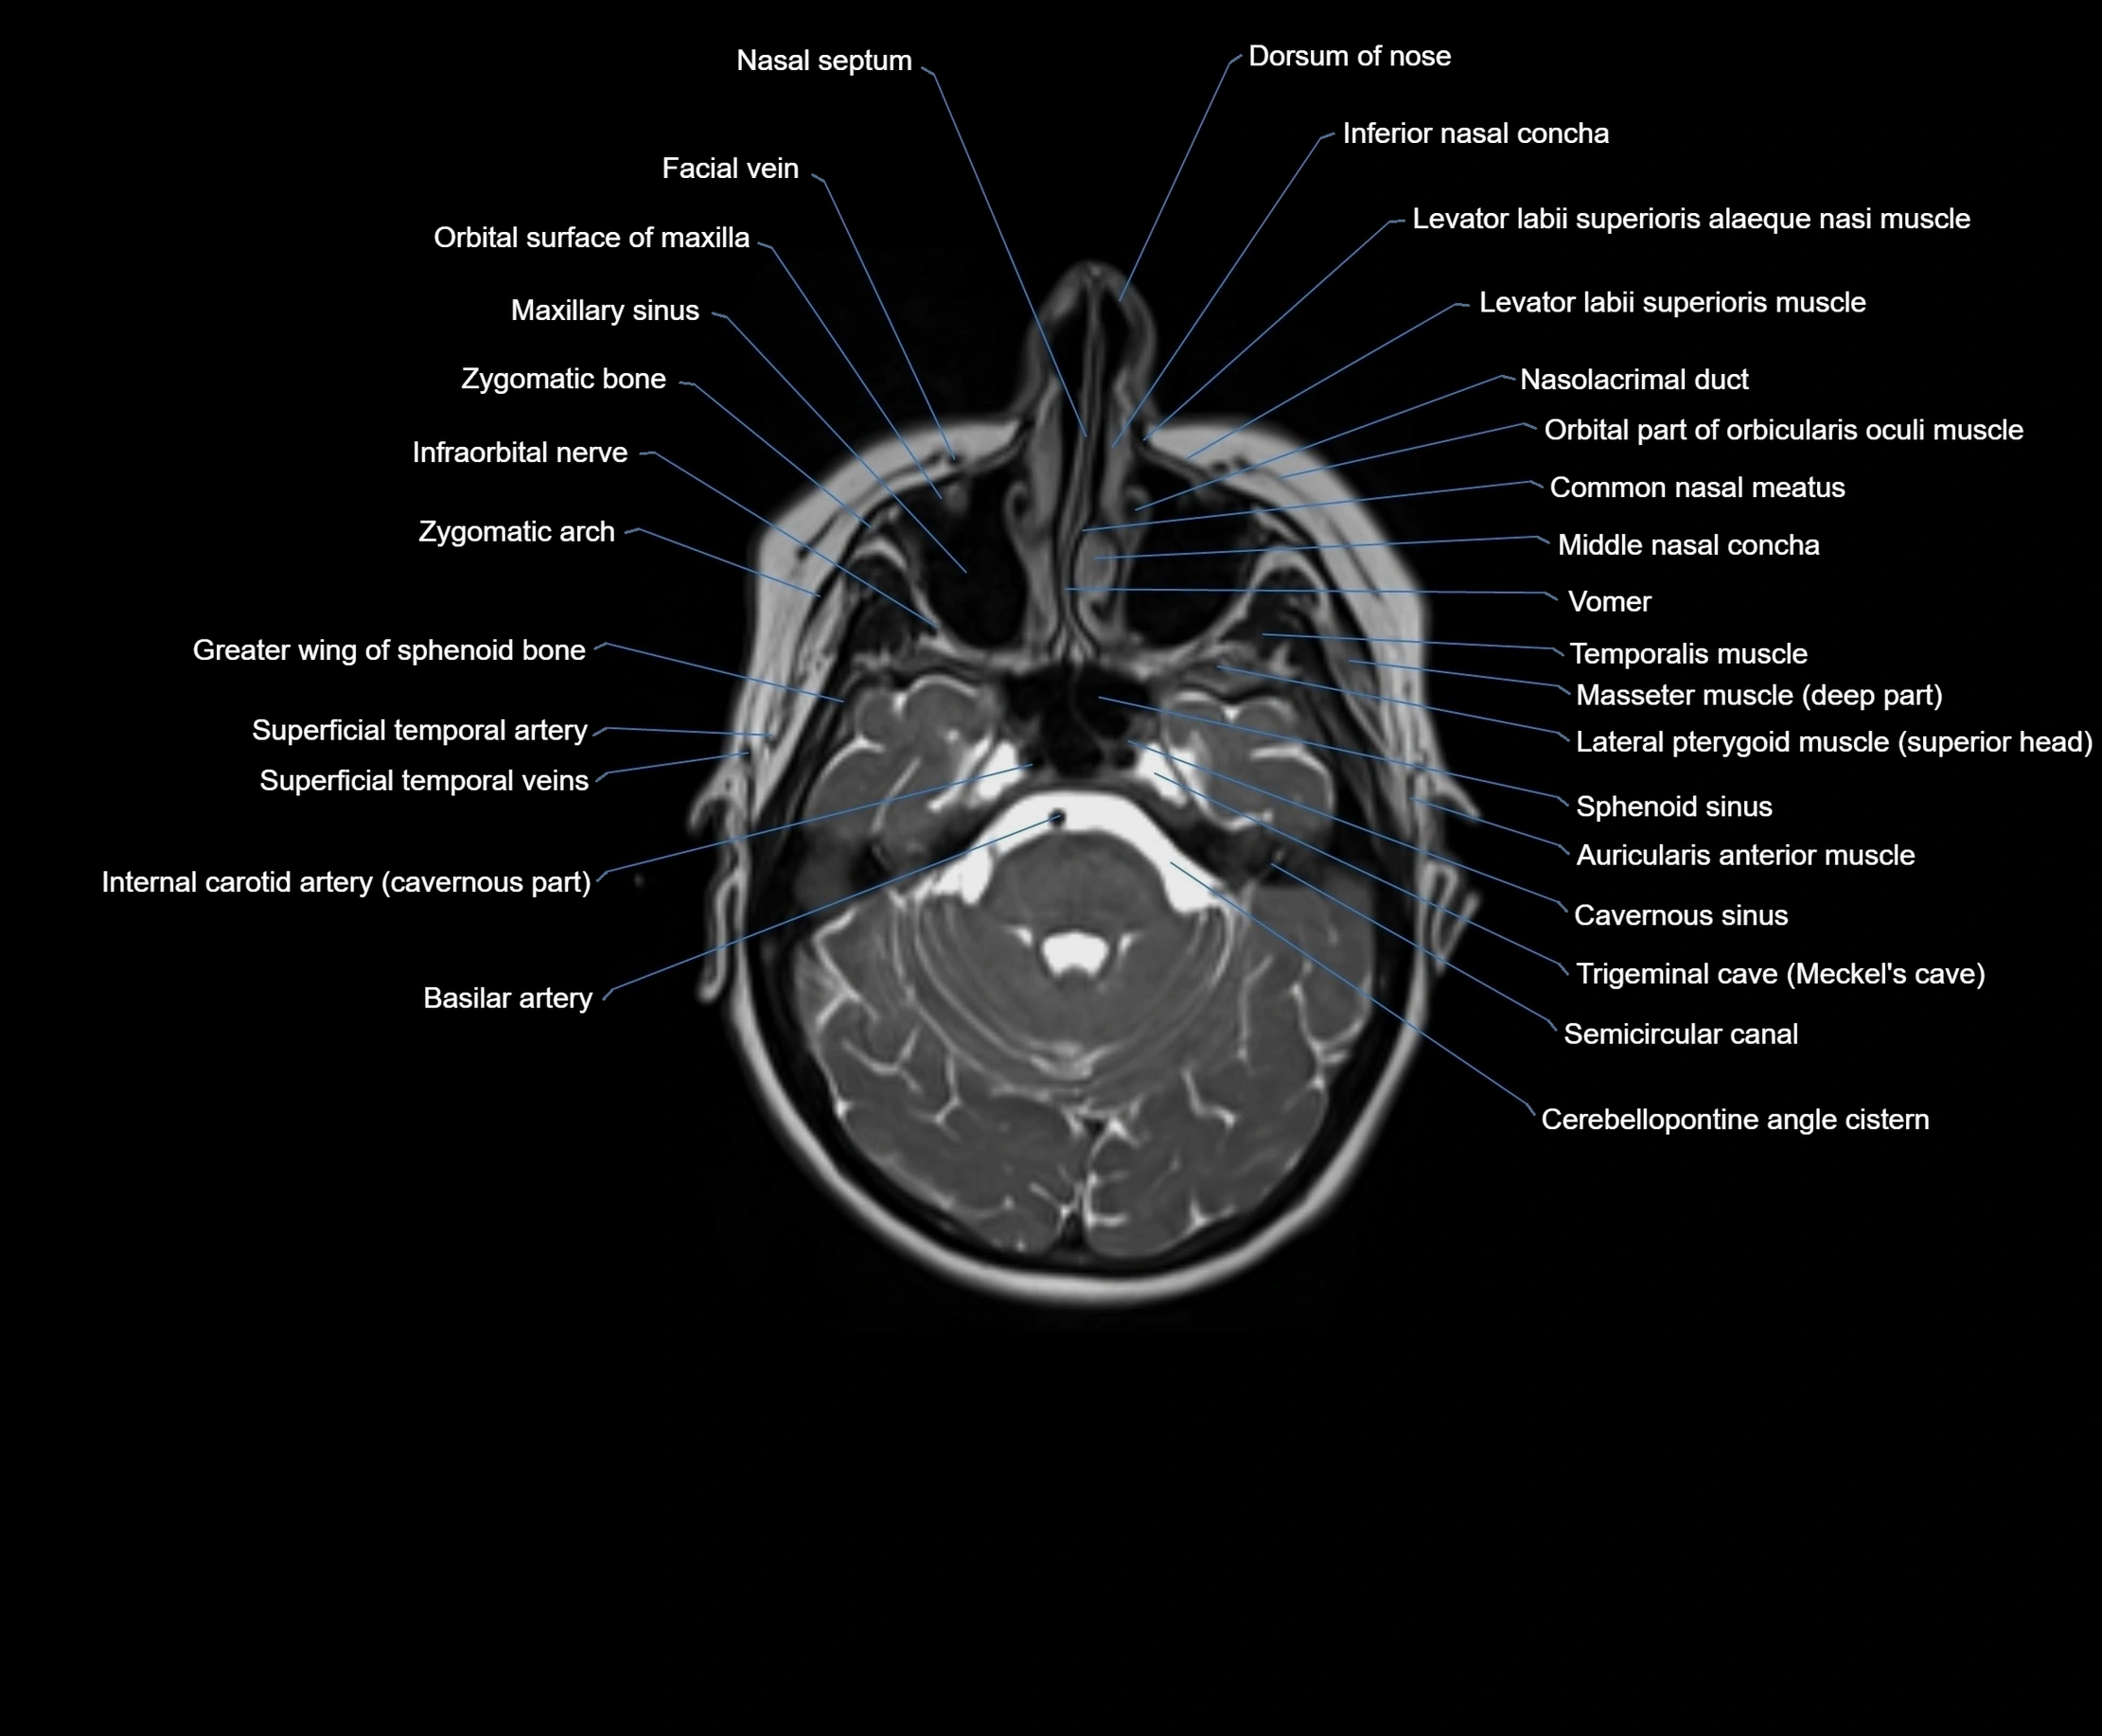

MRI images